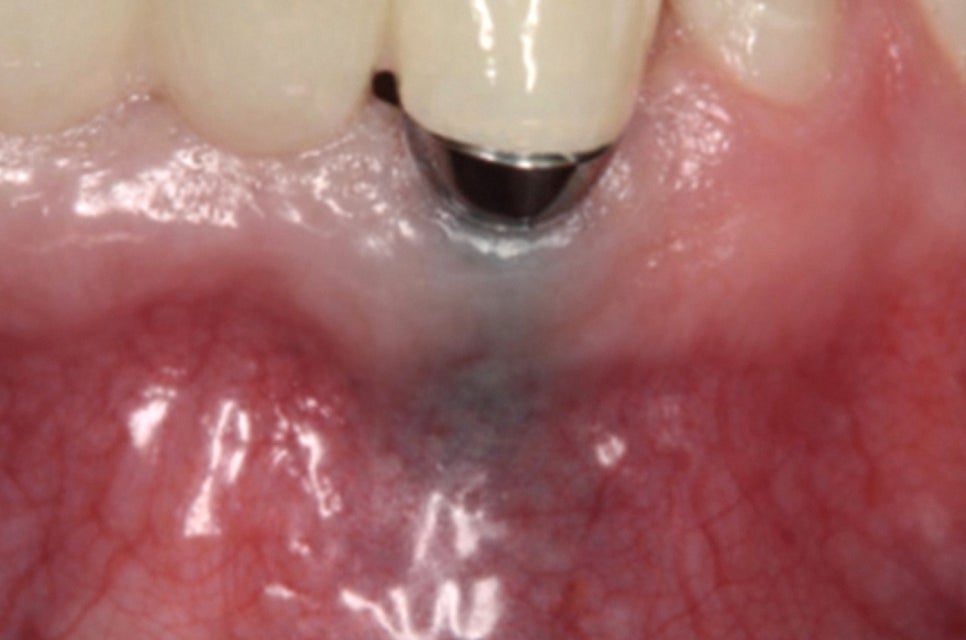

반면 임플란트 는 치조골에 직접 결합되는 구조로

이 과정에서 치주인대가 존재하지 않기 때문에

완충 역할을 하지 못합니다.

이는 저작력을 치조골이 직접적으로

받게 된다는 것을 의미하며,

과도한 압력이 가해지면 픽스처가

손상될 수 있는 위험을 증가시킵니다.

픽스처 주변 조직에 일어나는 염증으로

다음과 같은 원인에 의해 발생합니다.